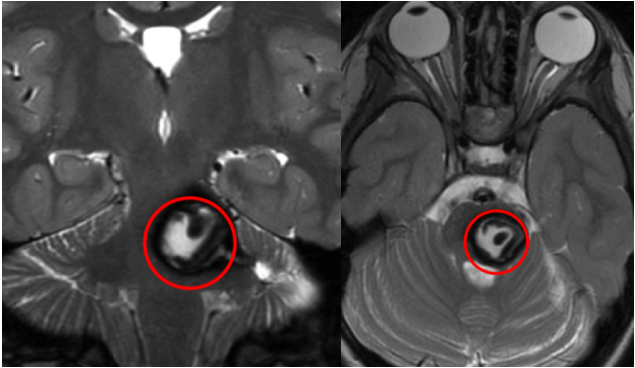

伽马刀治完不仅没好,走路越来越费劲,复查还说病灶变大了2022年,林女士拿着最新的MRI报告,满心焦虑。 两年前,她因运动后突发头晕、左腿疼痛查出脑干海绵状血管瘤,为降低风险选择伽...